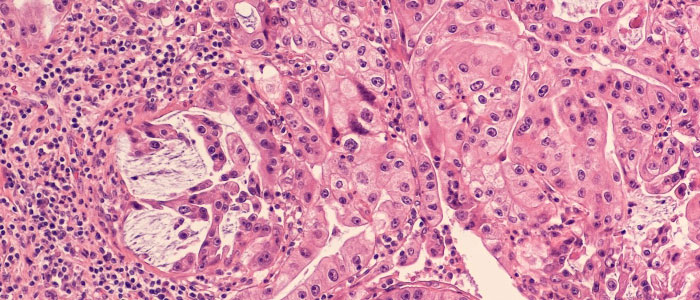

Scientists break new ground in potential treatment of common form of leukaemia

Glasgow researchers identify way to overcome chemotherapy-resistant leukaemia